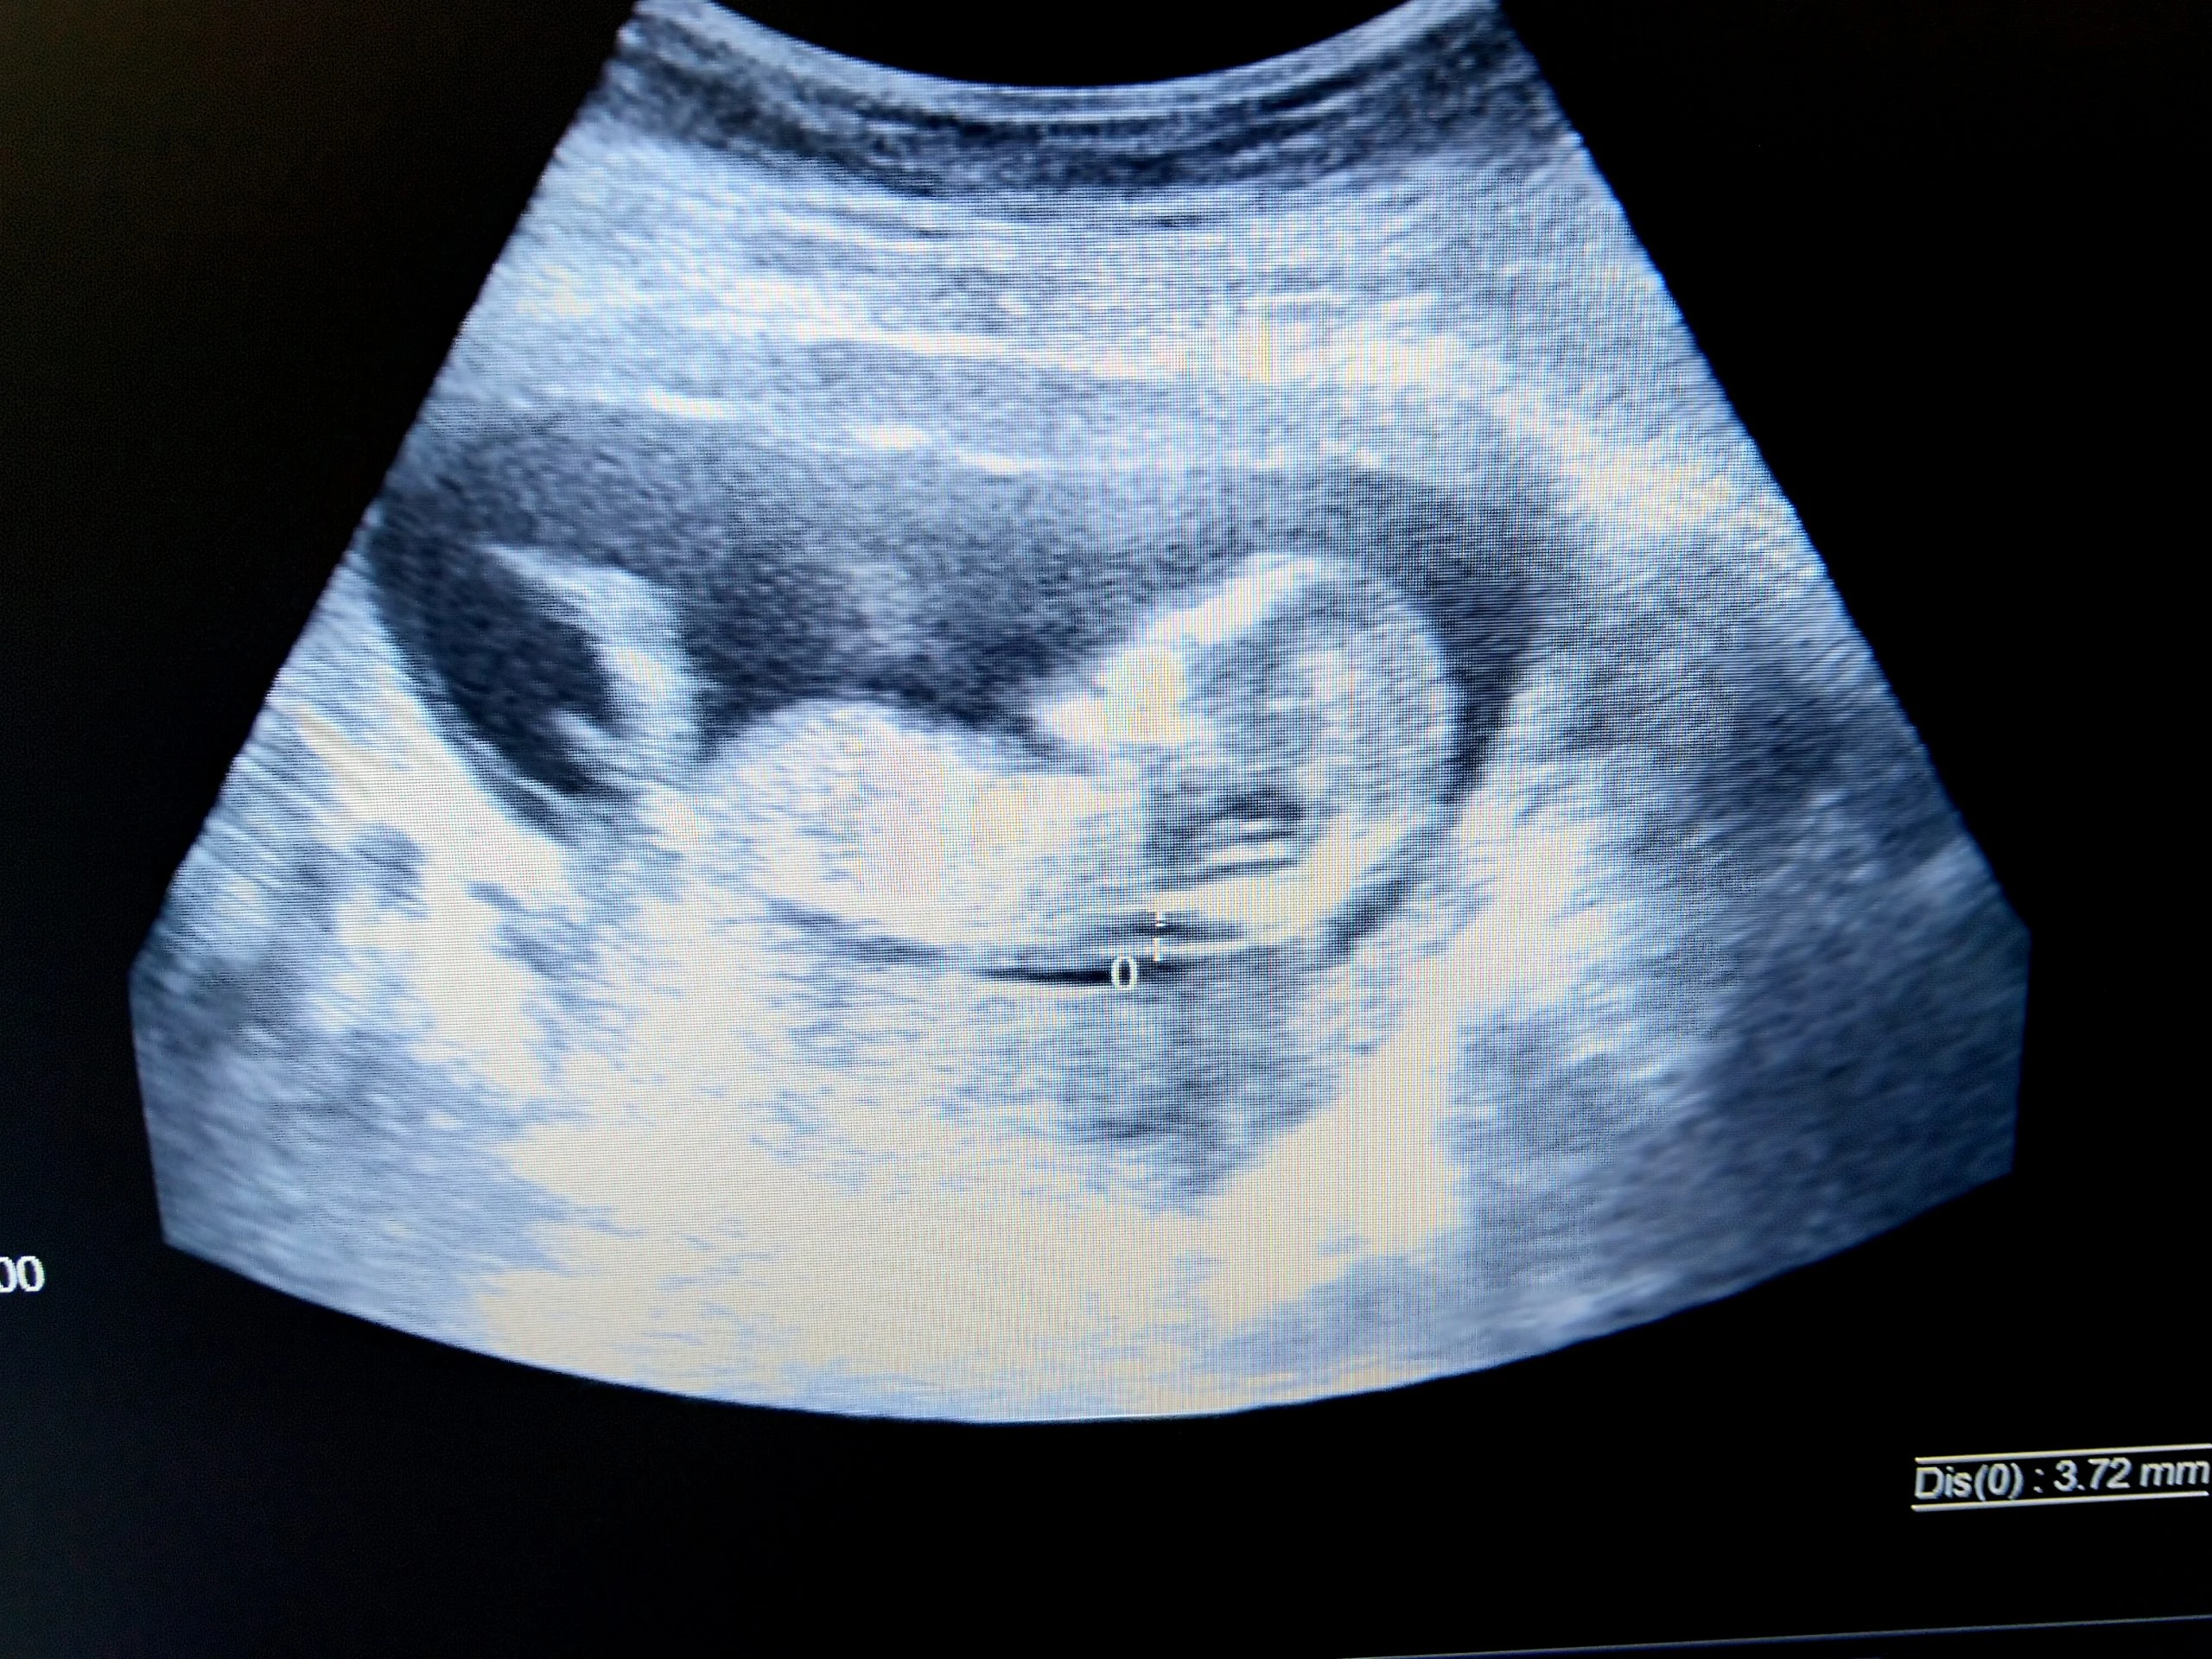

Quy trình siêu âm kiểm tra độ mờ da gáy thường được thực hiện khi thai nhi từ tuần 11 đến 13 tuần 6 ngày của thai kỳ – khoảng thời gian lý tưởng giúp đảm bảo độ chính xác của kết quả. Nhằm phát hiện sớm nguy cơ mắc dị tật bẩm sinh, đặc biệt là hội chứng Down, quy trình này bao gồm nhiều bước chuẩn bị và thực hiện cụ thể. Nhờ khả năng cung cấp hình ảnh chi tiết, siêu âm độ mờ da gáy giúp hiểu rõ hơn về tình trạng phát triển của thai nhi, làm cơ sở cho các quyết định y tế cần thiết sau đó.

Các bước thực hiện siêu âm

Quy trình siêu âm độ mờ da gáy bao gồm nhiều bước cơ bản, giúp đảm bảo tối đa độ chính xác và độ tin cậy của kết quả thu được.

- Chuẩn bị: Trước tiên, mẹ bầu không cần có bất kỳ sự chuẩn bị phức tạp nào. Thông thường, không yêu cầu ăn uống kiêng kỵ trước khi vào phòng siêu âm. Bác sĩ sẽ thực hiện thủ tục kiểm tra tuổi thai thông qua chiều dài đầu mông (CRL) của thai nhi, đảm bảo thai nhi phải có độ dài trong khoảng từ 45 mm đến 84 mm.

- Tiến hành siêu âm: Trong lúc thực hiện, bác sĩ sẽ bôi một lớp gel lên bụng mẹ bầu để tăng độ dẫn truyền sóng siêu âm, giúp hình ảnh thu được rõ ràng hơn. Nếu vấn đề về độ dày của mô da hoặc vị trí tử cung làm cho việc thực hiện qua bụng khó khăn, có thể áp dụng đầu dò qua âm đạo. Bước này giống như việc bạn điều chỉnh ống kính máy ảnh để chụp được bức hình rõ nét nhất về điều mình muốn quan sát.

- Đo kiểm tra: Đo độ mờ da gáy thực hiện qua nhiều lần để đảm bảo chính xác. Bác sĩ sẽ đo độ dày lớp dịch ở vùng gáy và sử dụng kết quả trung bình của các lần đo để làm dữ liệu cuối cùng. Đây là thời điểm để phát hiện các bất thường có thể xảy ra, như độ mờ Độ mờ da gáy trên 3 mm.

- Kết quả và theo dõi: Sau khi lấy đủ dữ liệu, bác sĩ sẽ phân tích kết quả và đưa ra khuyến cáo cần thiết. Khi phát hiện dấu hiệu bất thường, những xét nghiệm bổ sung như xét nghiệm Double Test hay chọc ối có thể được chỉ định. Toàn bộ quá trình này giúp đảm bảo rằng mẹ bầu và bác sĩ có được thông tin chính xác nhất về tình trạng phát triển của thai nhi.